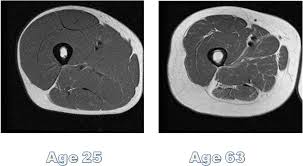

As early as your 30’s you begin to experience sarcopenia http://www.webmd.com/healthy-aging/sarcopenia-with-aging

“Researchers believe the following factors play a role:

- Age-related reduction in nerve cells responsible for sending signals from the brain to the muscles to initiate movement

- A decrease in the concentrations of some hormones, includinggrowth hormone, testosterone, and insulin-like growth factor

- A decrease in the body’s ability to synthesize protein

- Inadequate intake of calories and/or protein to sustain muscle mass”